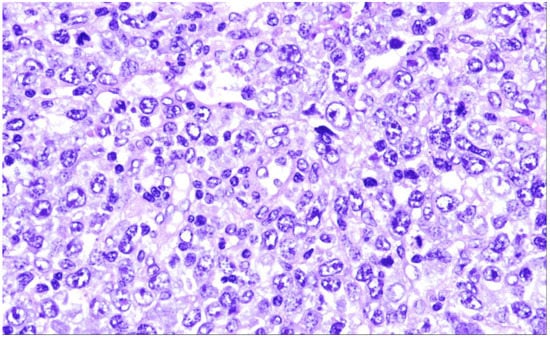

14. Plasmablastic Lymphoma

| Plasmablastic lymphoma |